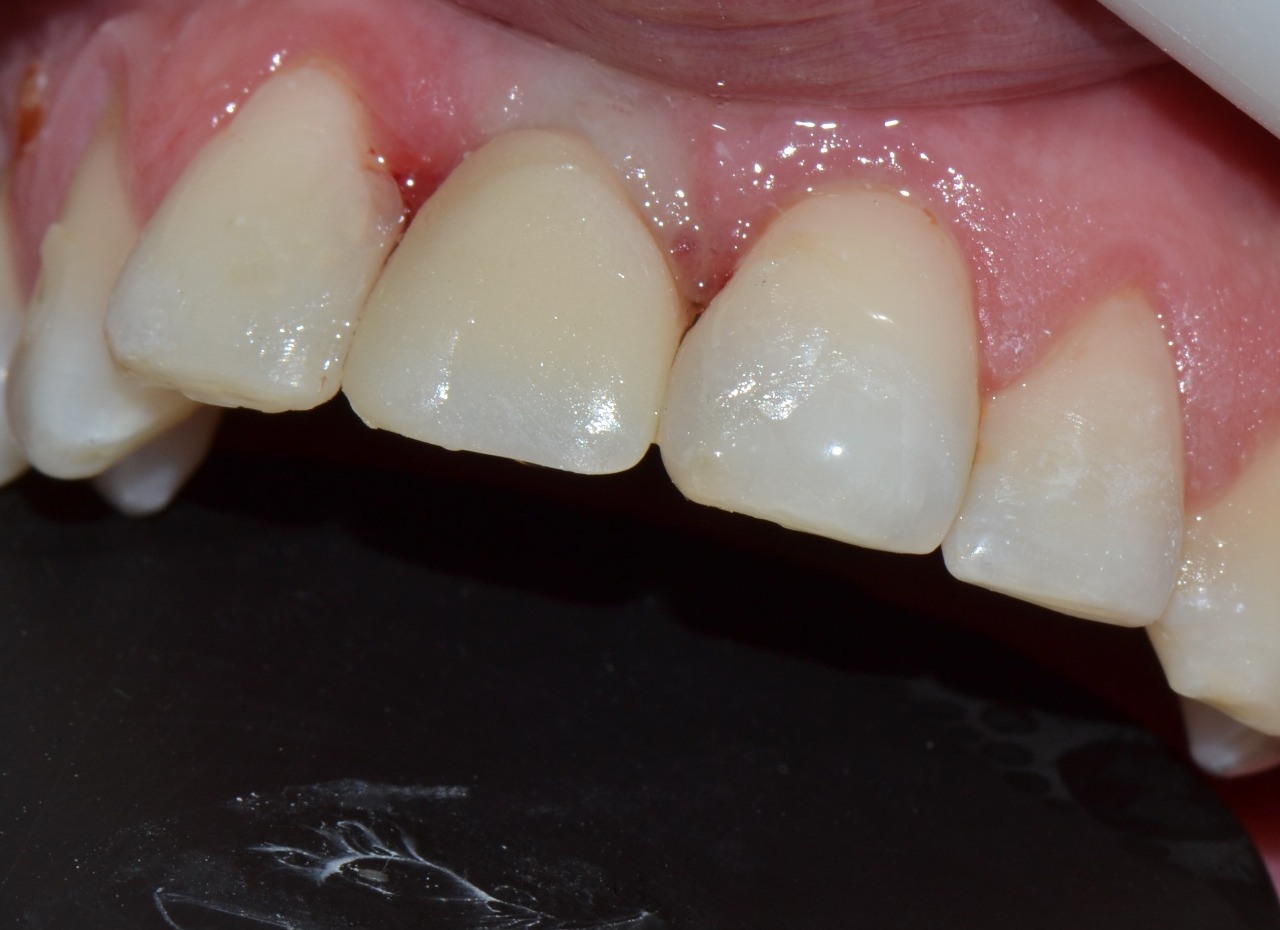

Os implantes dentários são diferentes dos dentes naturais em tamanho, forma, nível da crista óssea, e nível de mucosa. Após a remoção do tapa implante, a geometria do perfil do tecido é circular. Como os incisivos têm um perfil de tecido mais triangular, o tecido mole peri-implantar deve ser convertido para este formato.

O objetivo deste caso clínico foi estabelecer um perfil de emergência adequado. Buscou-se harmonia com a gengiva e área de contato proximal entre dentes adjacentes.

Além disso, foi definido a localização do zênite gengival e perfil peri-implantar numa forma triangular. Como resultado, seguindo o formato natural do dente.

Depois da osseointegração do implante, foi realizada a reabertura e instalação de um cicatrizador. Em seguida foi feita a moldagem e confecção de uma prótese provisória em resina acrílica (em laboratório) para condicionar o tecido periimplantar da região e proporcionar a reabilitação protética definitiva. Foram realizadas restaurações em resina nos elementos 12 e 21 para condicionamento adequado das papilas interdentárias.